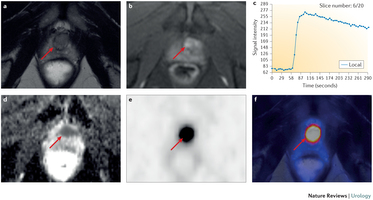

Foto: scanbeelden van 50 jarige prostaatkankerpatient die PSMA scan kreeg.

Currently, the findings of imaging procedures used for detection or staging of prostate cancer depend on morphology of lymph nodes or bone metabolism and do not always meet diagnostic needs. Prostate-specific membrane antigen (PSMA), a transmembrane protein that has considerable overexpression on most prostate cancer cells, has gained increasing interest as a target molecule for imaging. To date, several small compounds for labelling PSMA have been developed and are currently being investigated as imaging probes for PET with the 68Ga-labelled PSMA inhibitor Glu-NH-CO-NH-Lys(Ahx)-HBED-CC being the most widely studied agent. 68Ga-PSMA–PET imaging in combination with multiparametric MRI (mpMRI) might provide additional molecular information on cancer localization within the prostate. In patients with primary prostate cancer of intermediate-risk to high-risk, PSMA-based imaging has been reported to improve detection of metastatic disease compared with CT or mpMRI, rendering additional cross-sectional imaging or bone scintigraphy unnecessary. Furthermore, in patients with biochemically recurrent prostate cancer, use of 68Ga-PSMA–PET imaging has been shown to increase detection of metastatic sites, even at low serum PSA values, compared with conventional imaging or PET examination with different tracers. Thus, although current knowledge is still limited and derived mostly from retrospective series, PSMA-based imaging holds great promise to improve prostate cancer management.